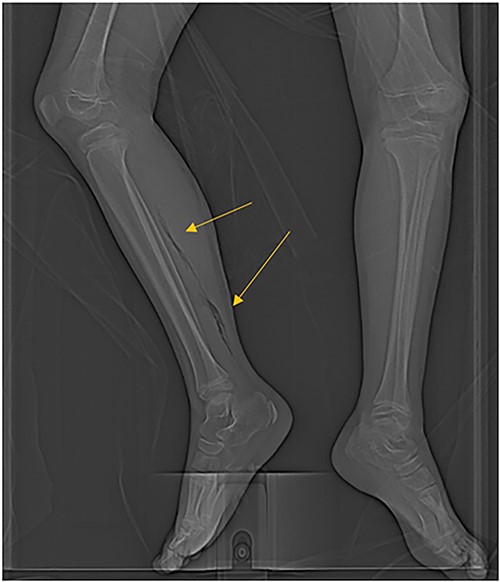

The patient was an 8-year-old female who presented to hospital with a 3-day history of fever, abdominal pain, and coffee ground emesis. On presentation, she was afebrile, tachycardic, and hypotensive. On examination, she had an acute abdomen and septic shock. Initial laboratory investigations revealed a venous pH of 7.08, CO2 of 47 mmHg, bicarbonate of 14 mmol/L, lactate of 3.9 mmol/L, white blood cell count of 3.7 × 109/L with an absolute neutrophil count of 0.96 × 109/L, C-reactive protein of 389 g/L, INR of 1.7, PTT 36 s, fibrinogen of 5 g/L, and an acute kidney injury with a creatinine of 100 micromoles/L and urea of 10 mmol/L. An abdominal ultrasound revealed a starry sky appearance of the liver with moderate free fluid in the right upper quadrant. She was not fluid-responsive and thus was treated with an epinephrine infusion and empiric antimicrobial therapy with ceftriaxone and vancomycin. Transportation was arranged to a tertiary care center with access to pediatric intensive care and surgical services. In transport she developed mild erythema to the right calf with severe pain to palpation and dorsiflexion out of proportion of clinical findings (Fig. 1). Her creatine kinase level was 10 000 U/l and a computerized tomography (CT) scan of the right leg demonstrated extensive soft tissue gas and myonecrosis (Fig. 2). An abdominal CT scan demonstrated evidence of bowel perforation in the right lower quadrant with associated loculation, intra-abdominal free air and fluid, and proximal bowel dilation (Fig. 3). Considering these findings, antibiotics were broadened to piperacillin-tazobactam, vancomycin, and clindamycin, and she was urgently taken to the operating room.

CT scan demonstrating extensive air in the soft tissue of the right leg.